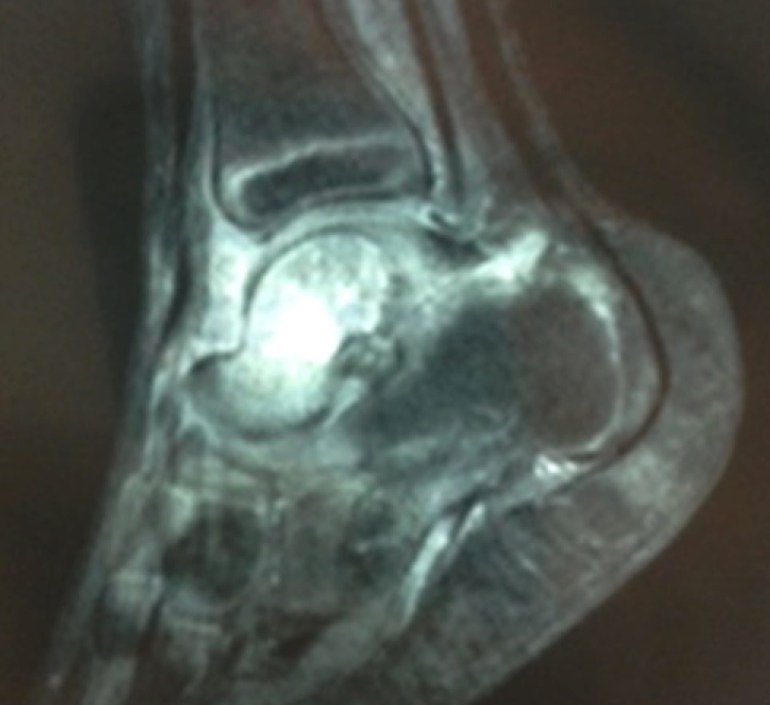

An MRI of his left foot was done.

MRI of the young boy’s left foot, showing increased signal intensity around his talus bone.